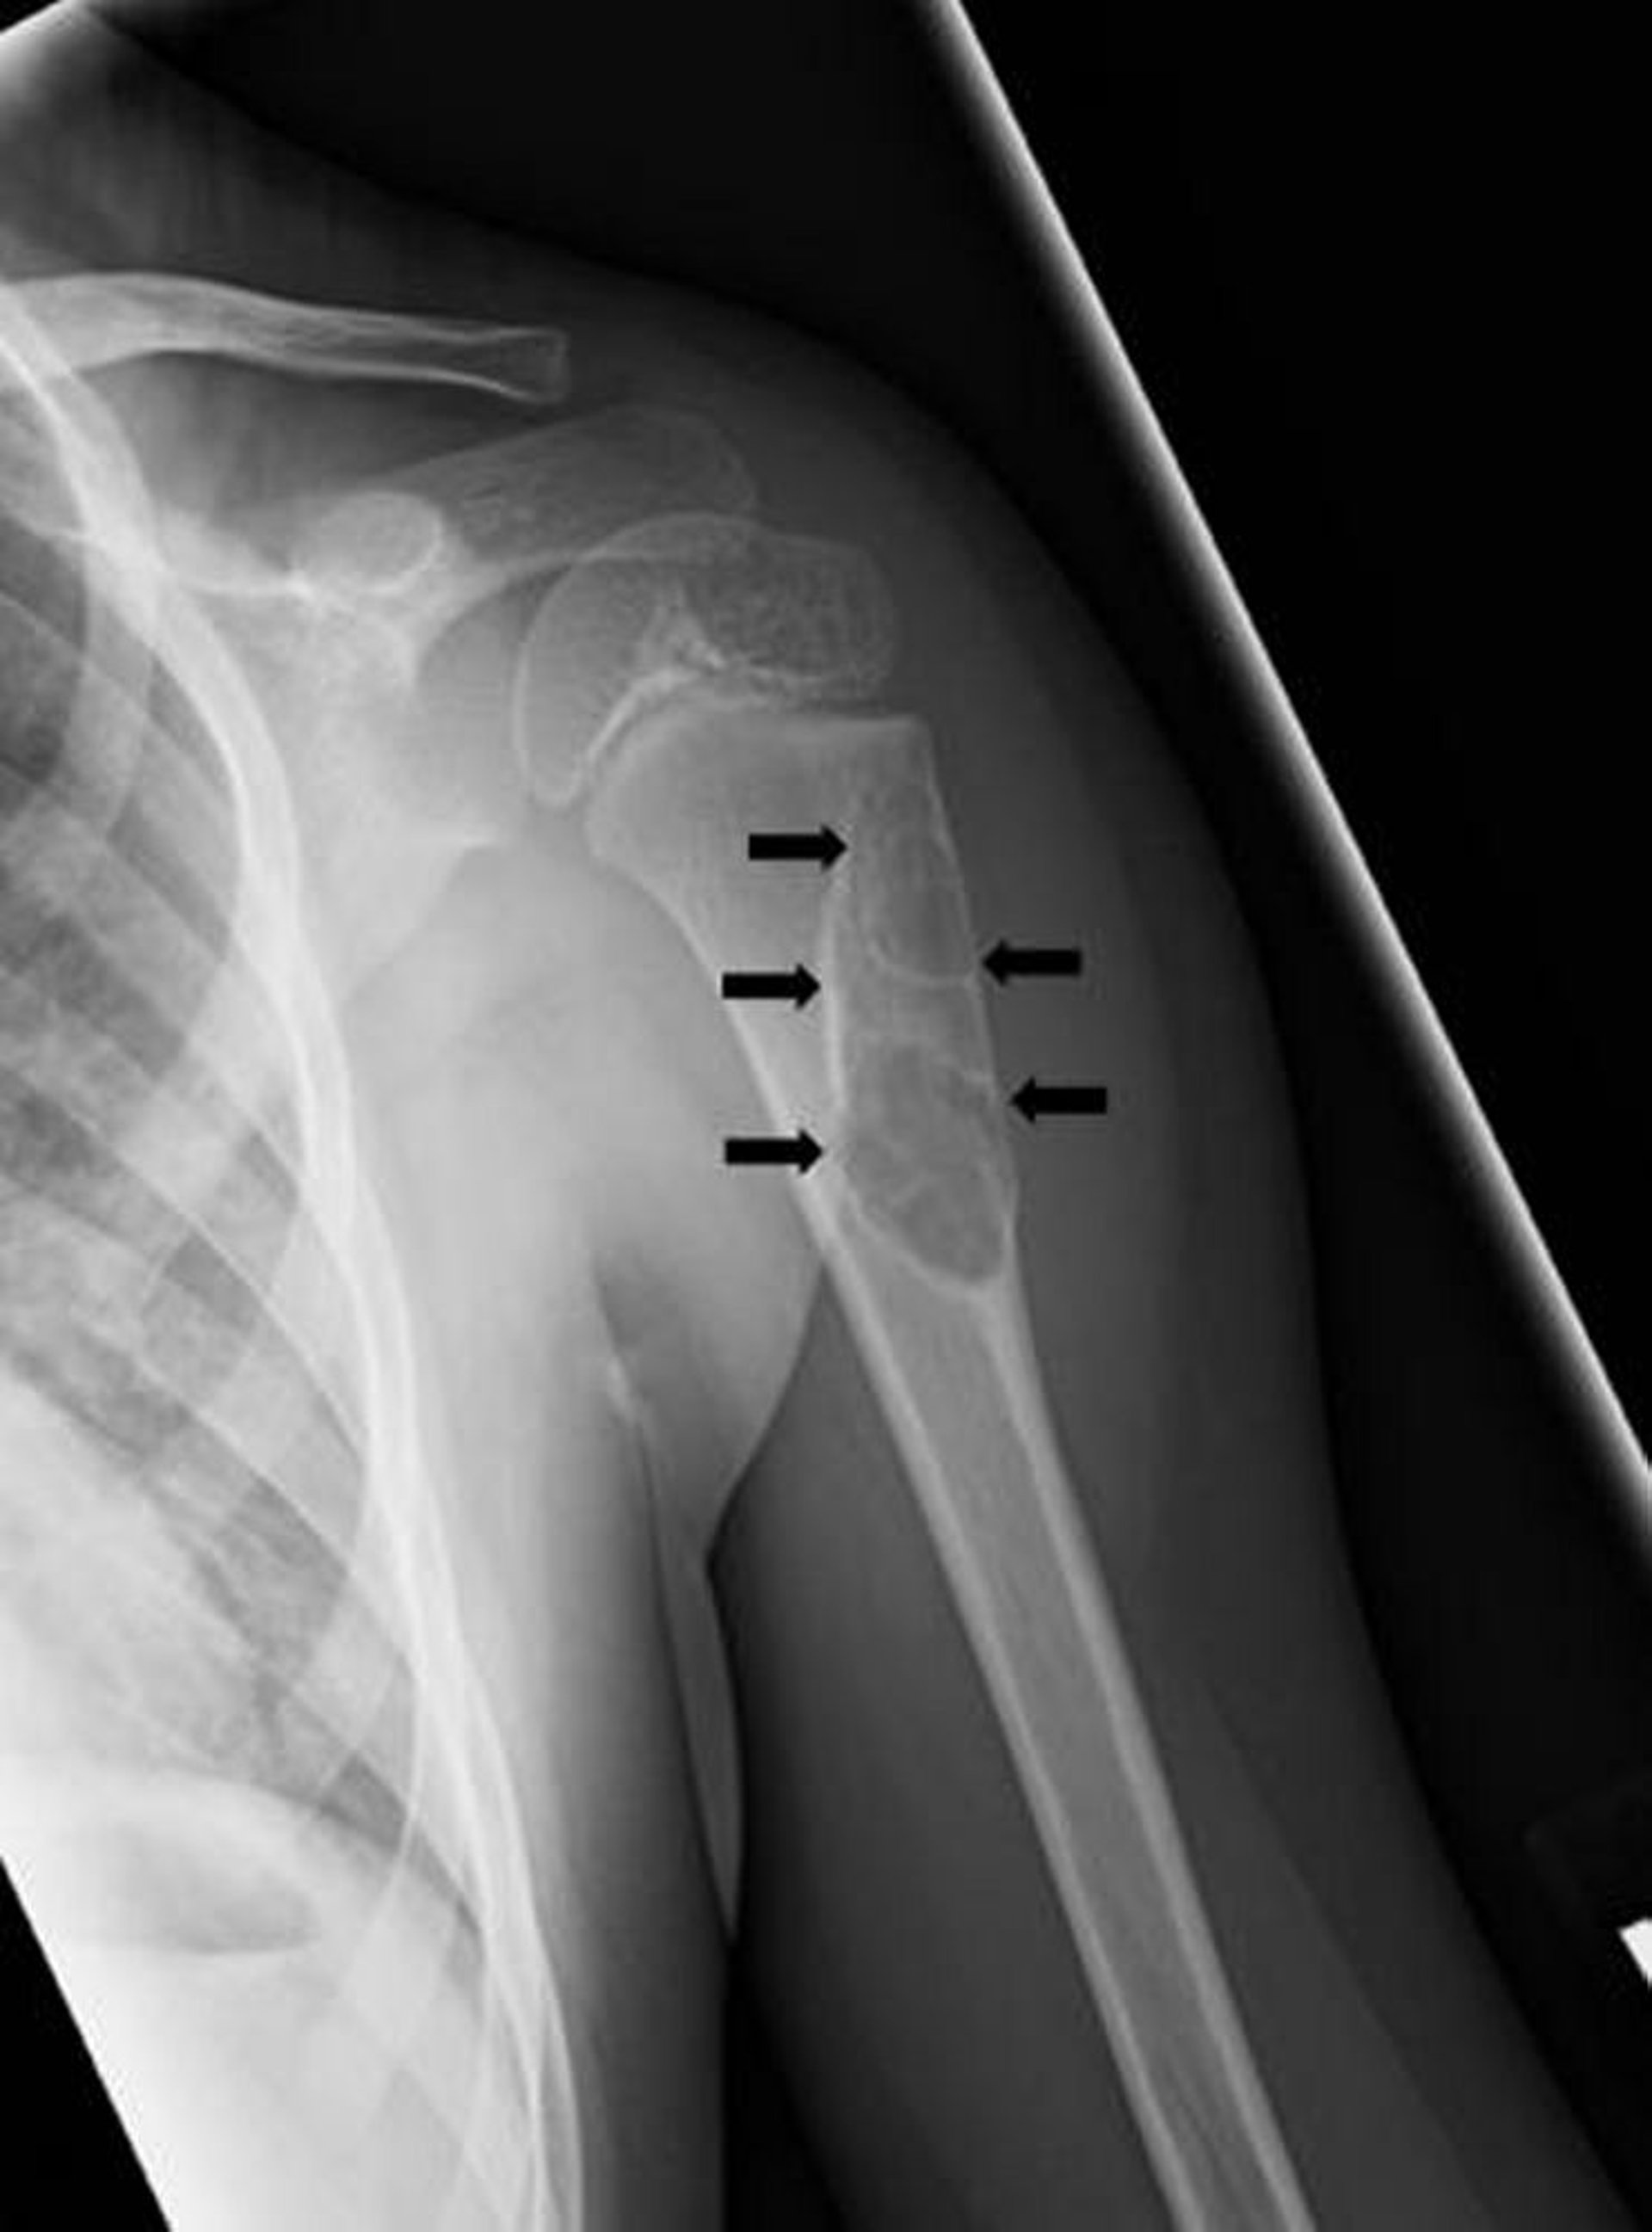

Kyste osseux solitaire

Cette radiographie montre une lésion kystique (flèches) de l'humérus chez un enfant compatible avec un kyste osseux unicaméral.

Image courtoisie de Michael J. Joyce, MD, and Hakan Ilaslan, MD.